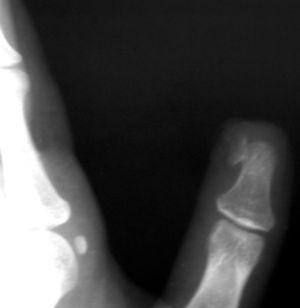

Figura 4.

Descripción de la radiología

Radiográficamente la mano: excrecencia ósea en forma de copa, que mostraba continuidad con el tercio distal de la falange distal, y producía alteraciones en la superficie de las partes blandas adyacentes (fig. 4).

La sospecha diagnóstica debe confirmarse radiográficamente en dos proyecciones: anteroposterior y lateral. Se observa una protusión exofítica de hueso trabecular, en forma de copa, localizada en el dorso de la falange distal. La capa distal fibrocartilaginosa que recubre la excrecencia ósea no puede visualizarse en la radiografía simple9. La resonancia magnética nuclear podría ser útil para identificar pequeños focos de osificación en el lecho ungueal10.